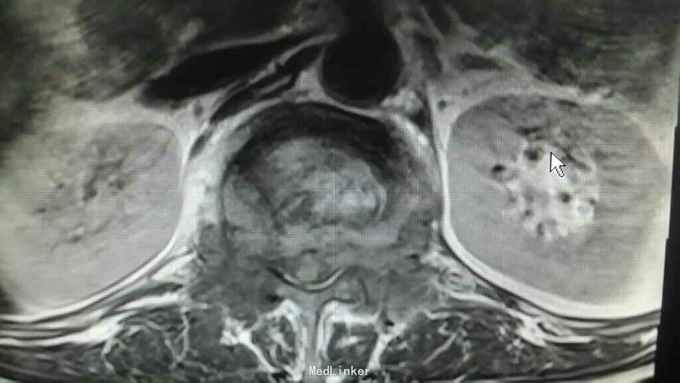

查体:脊柱生理曲度存在,无明显前凸,侧弯或后凸畸形,约胸10至腰5节段压痛及叩击痛阳性,双下肢肌张力正常,双侧股四头肌肌力约三级,双侧足背伸肌,踇背伸肌肌力约四级,双侧“4”字试验阴性,双侧直腿抬高试验阴性。肛周约15cm范围皮肤感觉减退。 辅助检查:肿瘤标志物无明显异常,血沉达120mm/h,血红蛋白111g/l,球蛋白与白蛋白比值倒置,血免疫球蛋白IgG达46.2g/l,明显升高。血清Kappa轻链与血清Lambda轻链比值明显升高。余辅助检查见下图。

通过影像学,实验室检查,骨髓穿刺检查及行CT引导下穿刺病理结果,患者多发性骨髓瘤诊断已明确。于全麻下行“腰1椎体病理性骨折病变清除减压内固定术”,术中可见病变压迫脊髓明显,彻底减压,术中出血较多,椎体破坏较重,未予骨水泥塑型,术后患者症状缓解明显,拆线后转至血液科进一步治疗。

多发性骨髓瘤是一种单克隆的浆细胞异常增生所致的恶性肿瘤,常以骨骼症状为首发,以脊柱最常累及,本例患者主要手术指征为持续且无法缓解的骨痛,并存在脊髓和神经根压迫症状,,主要影像学表现为穿凿样溶骨性改变,周围无硬化改变。很多全身骨现象无明显的阳性表现,增加了诊断的难度,上面提到的血沉升高,贫血,球白比倒置,血免疫球蛋白升高,骨髓穿刺综合判断,诊断明确后,一般行姑息性手术治疗,一般预后较差,随访见到生存期最长为4年。